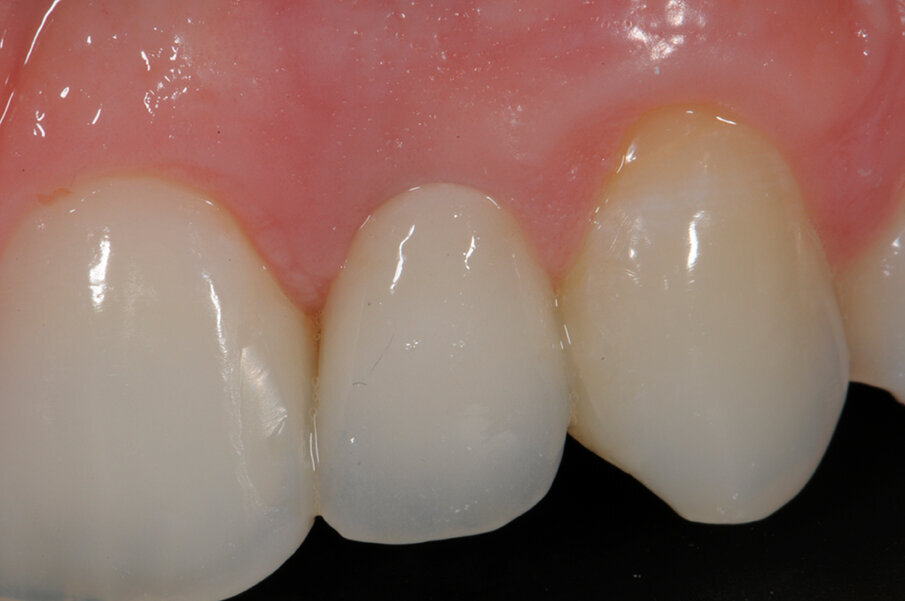

Fig. 2 - Foto inziali del caso. Si noti la presenza di elemento 12 di conformazione conoide e agenesia di elemento 22 sostituito con protesi tipo Maryland.

Fig. 7 - Controllo dei tessuti molli a 3 mesi, non è stato ancora riabilitato il conoide.

Fig. 8a - Caso concluso con veeners in ceramica a livello del 22.